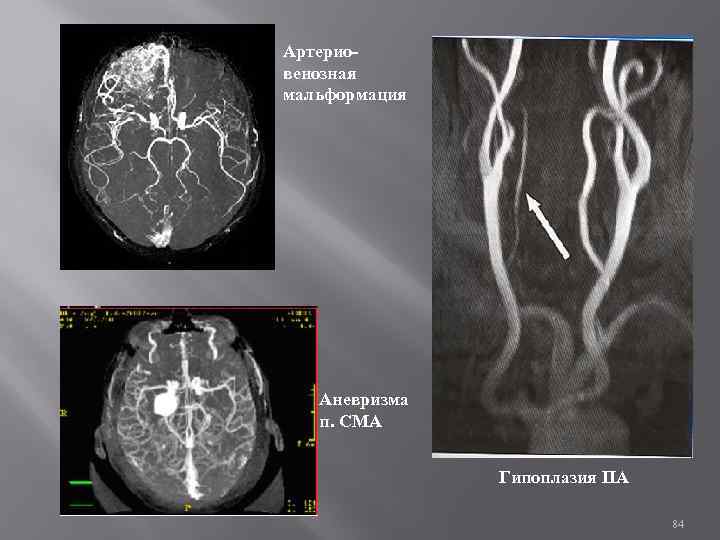

Магнитно-резонансная ангиография (МРА) на томографах с напряжённостью магнитного поля > 1. 0 Тесла отличие сигнала подвижной ткани (крови) от окружающих неподвижных тканей анатомические, функциональные особенности МК без использования рентгенконтрастных веществ четкое изображение - вещества на основе парамагнетиков - гадолиний 83

Артериовенозная мальформация Аневризма п. СМА Гипоплазия ПА 84